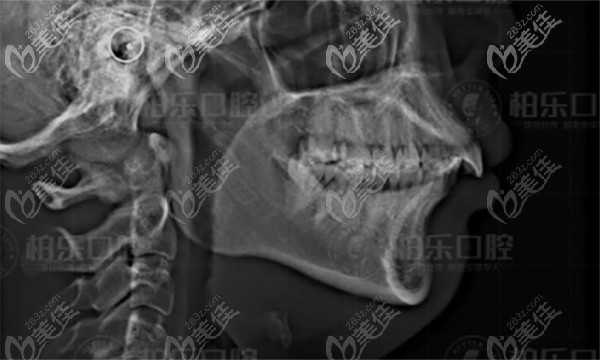

在見醫(yī)生之前先去拍片,南寧柏樂正畸醫(yī)生分析我的牙齒情況-原來我的嘴突和下巴短是由于深覆合深覆蓋導(dǎo)致的,給你們看看。